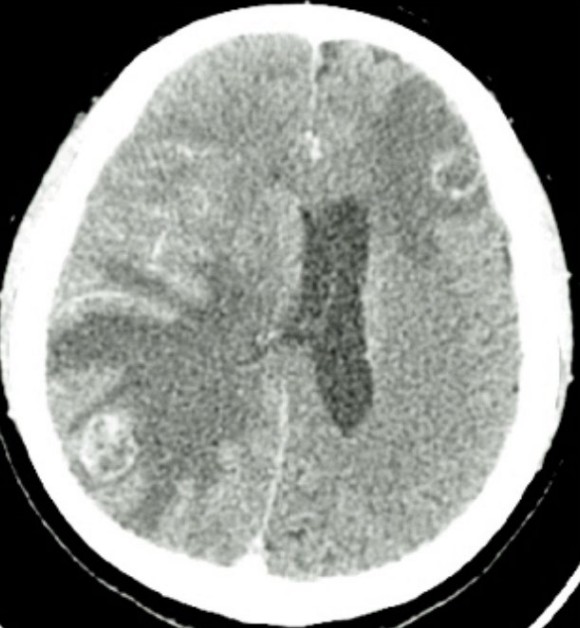

Seizure with ring-enhancing brain lesions

You receive a BAT call of a 34-year-old male from a local shopping centre. When the ambulance arrived, he was …